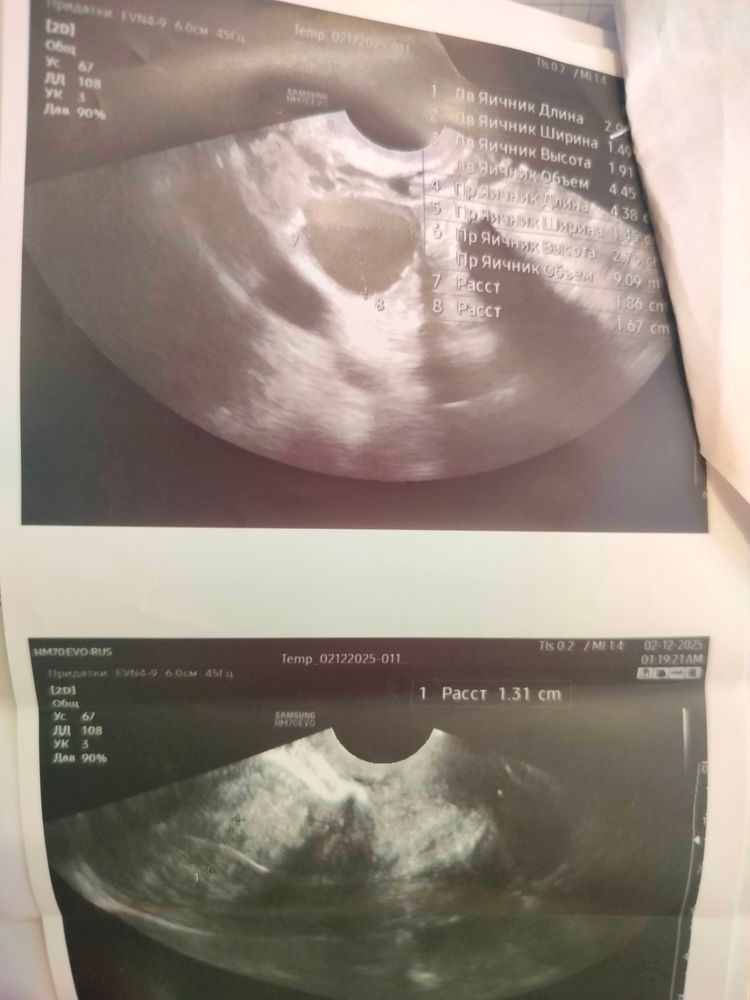

Доброго времени! Подскажите, пжлст, как считаете, была ли О, по моим подсчётам и ощущениям была 12-13 февр, была на приёме у врача в январе 13.01.25. на 27-ой дц. Цикл 32-33 дня. О всегда поздняя. По УЗИ эндометрий 15,1, однородный. В ПЯ структура не изменена, в ЛЯ ЖТ 23*14.

08.02.25 23 дц, без особенностей, эндометрий 10, в ЛЯ 6фол по 4-5 мм, в ПЯ 7фол по 6-10мм. ДФ не отметила.